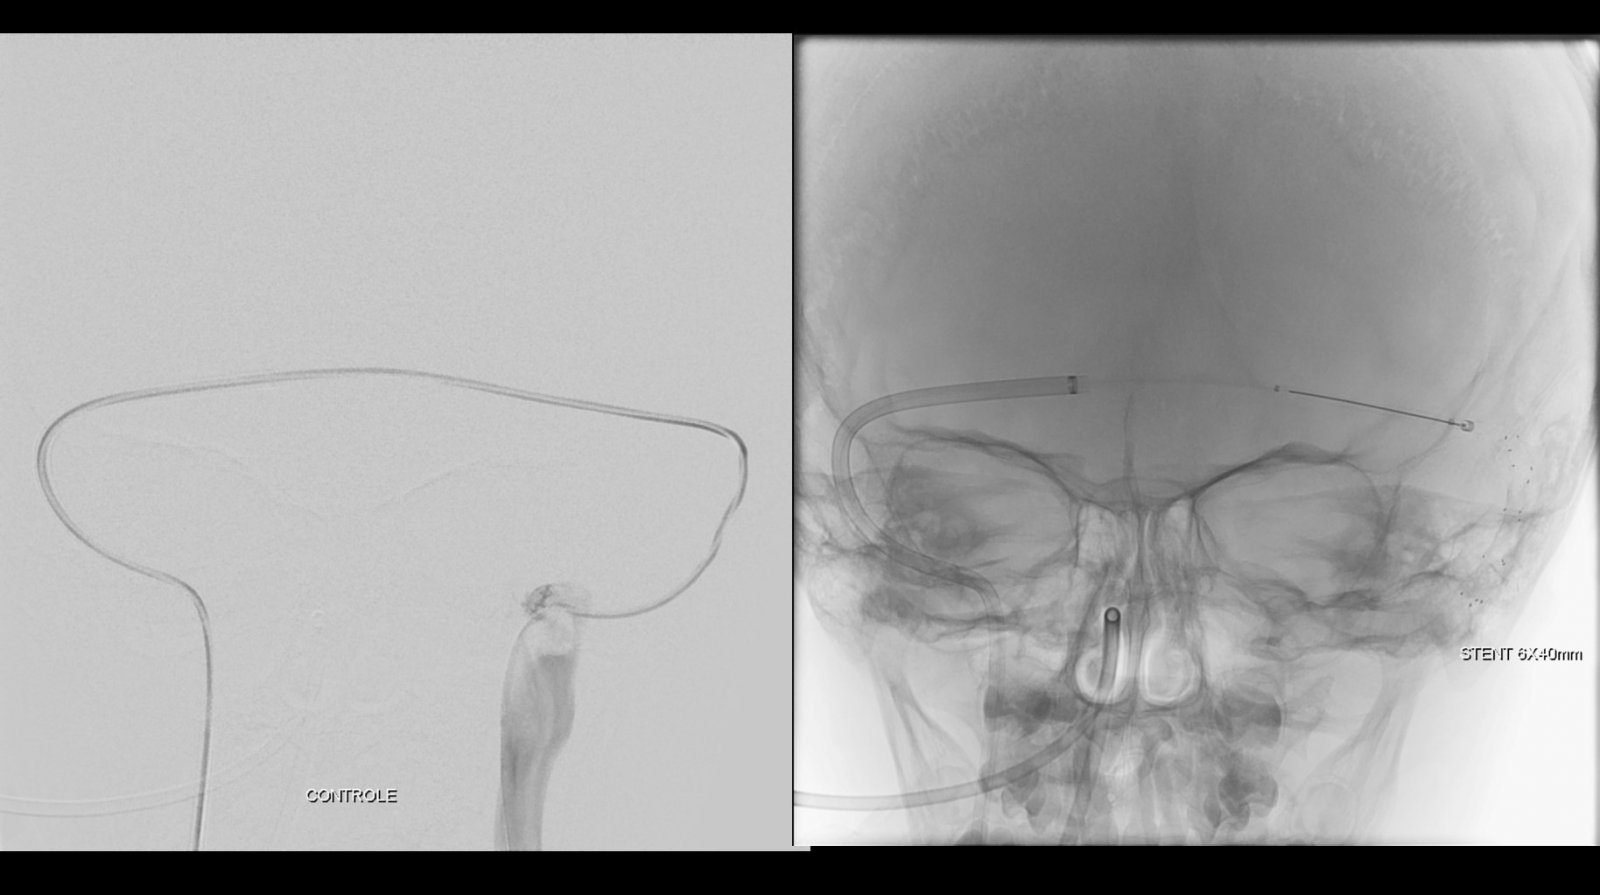

Foi realizada discussão entre as diversas especialidades, em vista da não melhora com o uso do anticoagulante, foi sugerido a tentativa de trombectomia mecânica do seio dural.

O caso clínico apresenta a utilização de materiais com finalidades primárias para trombectomia mecânica no contexto de acidente vascular cerebral (Rebar 27 + Solitaire) e o balão Copernic RC (Balt) comumente utilizado auxiliando na embolização de fístulas durais para os seios, auxiliando no processo de trombectomia mecânica no contexto de extensa trombose venosa cerebral.